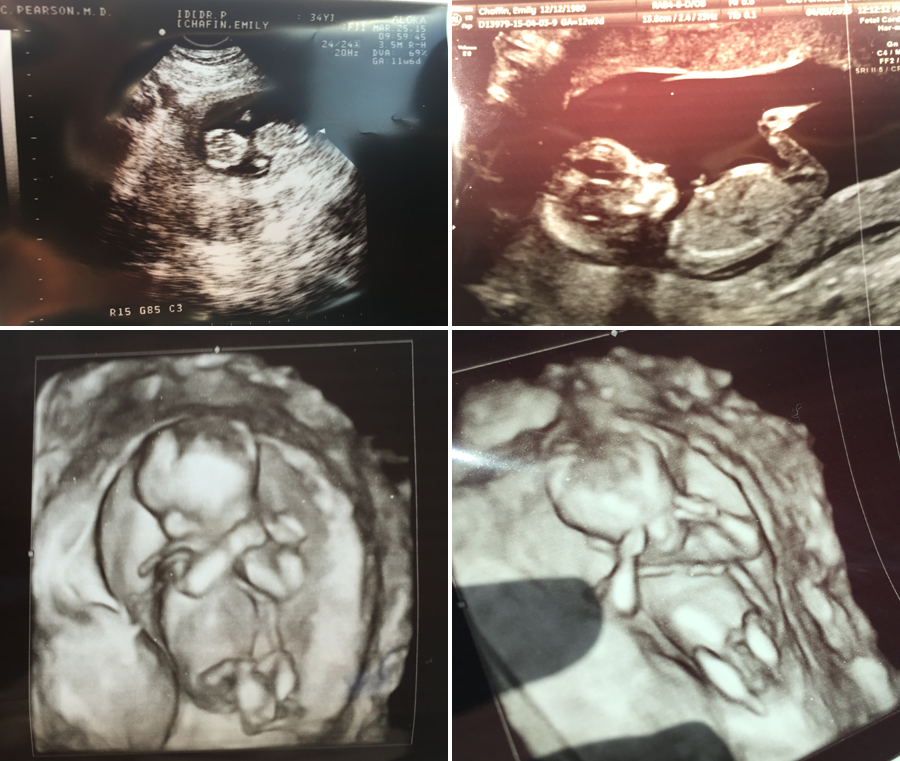

This is the ultrasound that blew our minds. It was 12 weeks, and we went to a place that did 3D ultrasounds as well. I mean, I didn't realize it actually looked like a small person until I saw this. That looks like a baby! This was the one we would show everyone, and it was so much fun to see their reaction.

This was also the ultrasound we showed our OB (a different Dr. did the ultrasound), and both him and the nurse said "it looked like a boy, but it was too soon to tell" (Spoiler alert: it's a girl).